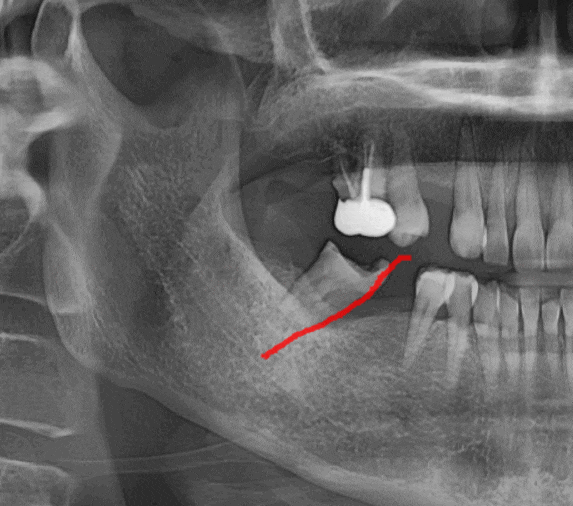

240423

옆에 붙어있던 치아가 없어지면

시간이 지나면서 옆으로 점점 기울어지거든요

빈 공간으로 눕는거죠

문제는 육안으로 볼 때에는

티가 안납니다.

환자분은 그럭저럭 씹을 수도 있어서

문제가 없다 생각하시지만

x-ray를 찍어보면...

이만큼 기울어져있답니다.